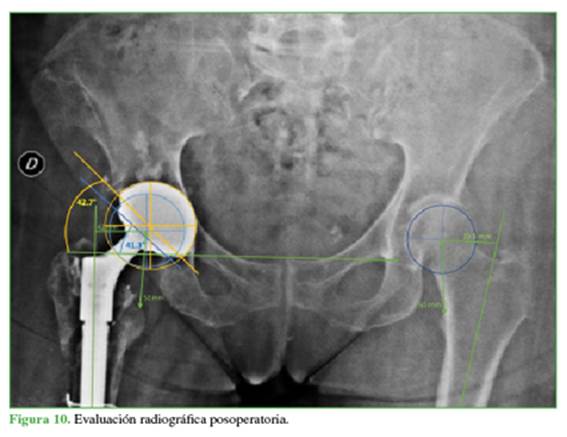

En el análisis radiológico posquirúrgico de la placa, se evidenció un incremento del offset horizontal, que pasó de 39 mm a 42 mm por el uso del offset extendido. Esto se determinó por el método por Bellova y cols.,16 en el cual se traza una línea que une los centros de rotación independientes de la copa no cementada y la copa DM. Al tener una orientación independiente, la copa DM presenta una inclinación de 41,3°, diferente de la copa no cementada (42,7°), lo que optimiza la inclinación y la anteversión. Se mejoró la discrepancia de miembros hasta lograr una diferencia de solo 1 mm (Figura 10). En la evaluación radiográfica a los 24 meses del procedimiento, se evidenció la consolidación completa del fémur proximal y no se encontraron cambios en los valores de inclinación, anteversión y offset, ni signos de aflojamiento en la interfaz entre la copa no cementada y la copa DM. Del mismo modo, no se observaron signos de aflojamiento en ninguno de los componentes (Figura 11).